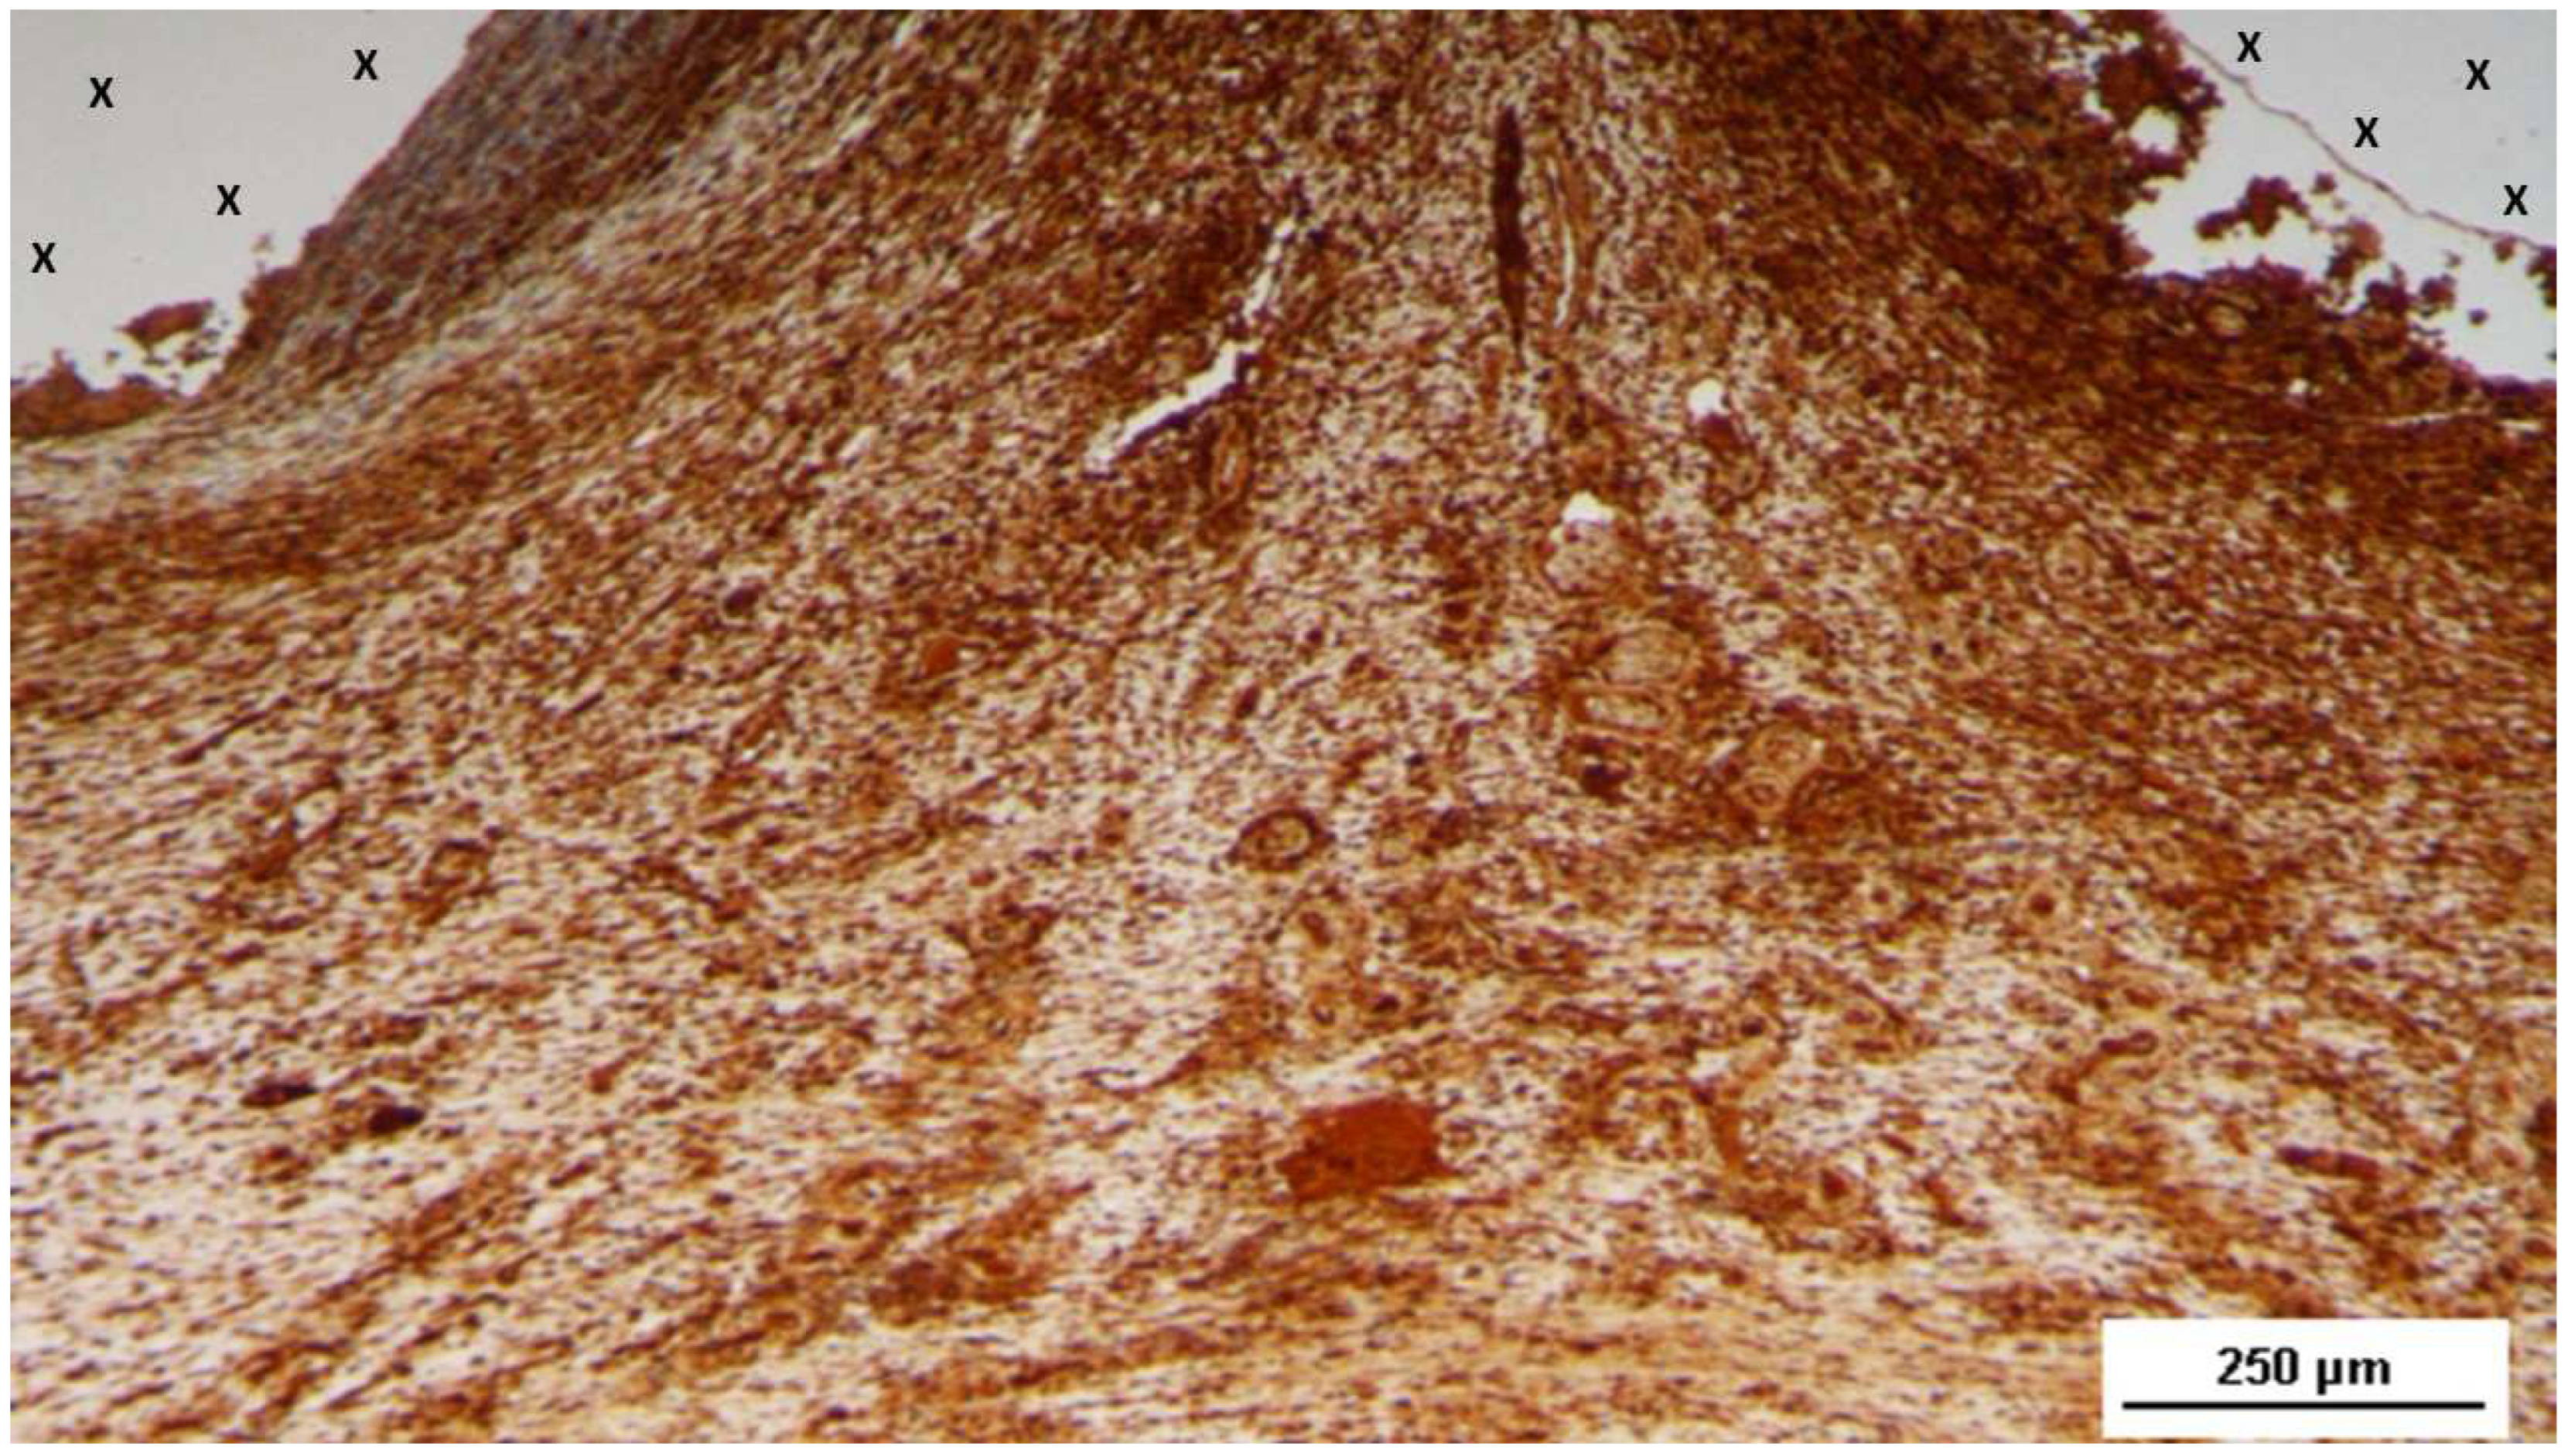

Figure 17. Tissue specimen removed 4 months post-implantation (Midterm - MT). Large numbers of NGF-positive elements (brown staining) are evident near the TPE fabric of the 3D scaffold (X). NGF 50X.

Regarding muscle development, biopsy samples obtained in the short-term period after implantation of the S&S 3D scaffold showed a high concentration of nerve growth factor (NGF)-positive cells within the thermoplastic elastomer (TPE) material of the 3D scaffold (Figure 15).

Table 16 The nascent myocytes exhibited prominent nucleoli, vesicular nuclei, and moderate basophilia, indicative of early myocytic differentiation. By the midterm phase, the number of NGF-positive cells had increased in the TPE fabric of the scaffold (Figure 17), corresponding with a more extensive and organized development of muscle fibers and larger bundles of muscle cells interspersed throughout the connective tissue adjacent to the scaffold. The muscle fibers showed small, spindle-shaped nuclei and eosinophilic cytoplasm, characteristic of progressing myocyte differentiation (Figure 18).